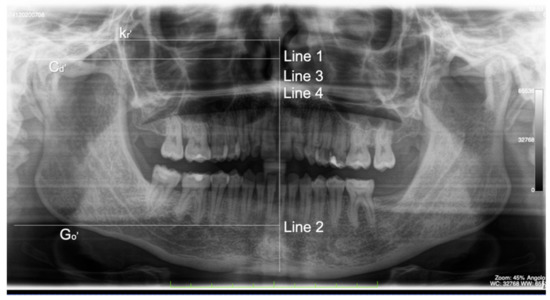

2. Clinical Case